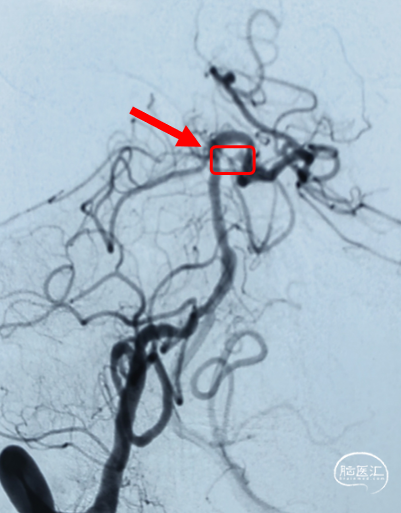

术前正位造影

术前通过反复造影确认,出血病灶为“小脑上动脉动脉瘤破裂出血”。

载瘤动脉-小脑上动脉

破裂出血动脉瘤